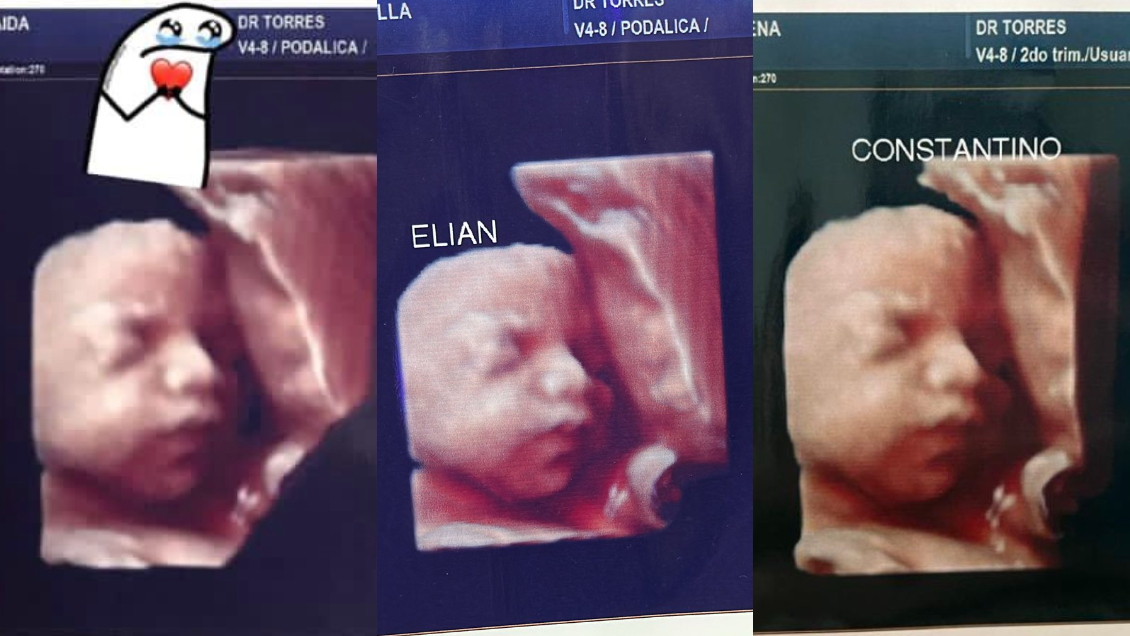

Un grupo de cuatro mujeres que se atendieron en la misma clínica denunciaron a través de redes sociales que les enviaron la misma imagen después de su ecografía.

Las cuatro mujeres descubrieron se dieron cuenta de la estafa cuando una de ellas compartió a través de TikTok la imagen de su "bebé".

"Ese no puede ser tu bebé (...) Tengo la misma imagen", le comentó una internauta, lo que encendió las alarmas.

"Por ahora somos 3 mamás a las que una clínica ESTAFÓ con una foto de un bebé que no es el nuestro. Está de más decir que encima que cobran carísimo uno se va ilusionado por ver a su bebé y tener un lindo recuerdo. Estamos en busca de más mamás con el mismo bebé", denunció otra mujer a través de Facebook.